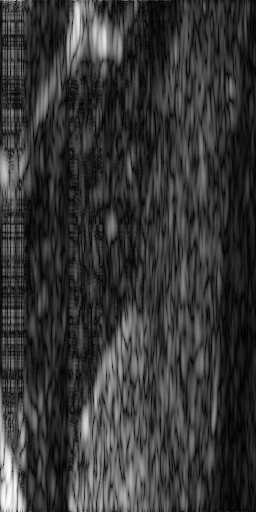

?figurename? 3: Image 1, subsampled at 50% and recovered with (a) ST-SBL 1/32 (Γ¯=2.22×1016¯Γ2.22superscript1016\bar{\Gamma}=2.22\times 10^{-16}), (b) BSBL-BO 32 (Γ¯=2.22×1016¯Γ2.22superscript1016\bar{\Gamma}=2.22\times 10^{-16}), (c) IRLS - Dual prior, (d) T-MSBL, (e) T-MSBL-MoG-4, (f) 128-sparse

?figurename? 4: Image 2, subsampled at 33% and recovered with (a) ST-SBL 1/32 (Γ¯=2.22×1016¯Γ2.22superscript1016\bar{\Gamma}=2.22\times 10^{-16}), (b) BSBL-BO 32 (Γ¯=2.22×1016¯Γ2.22superscript1016\bar{\Gamma}=2.22\times 10^{-16}), (c) IRLS - Dual prior, (d) T-MSBL, (e) T-MSBL-MoG-4, (f) 86-sparse

Figure 3 shows Image 1 after being subsampled at 50% and then recovered with various algorithms. Figure 4 shows the same for Image 2 after it was subsampled at 33%.